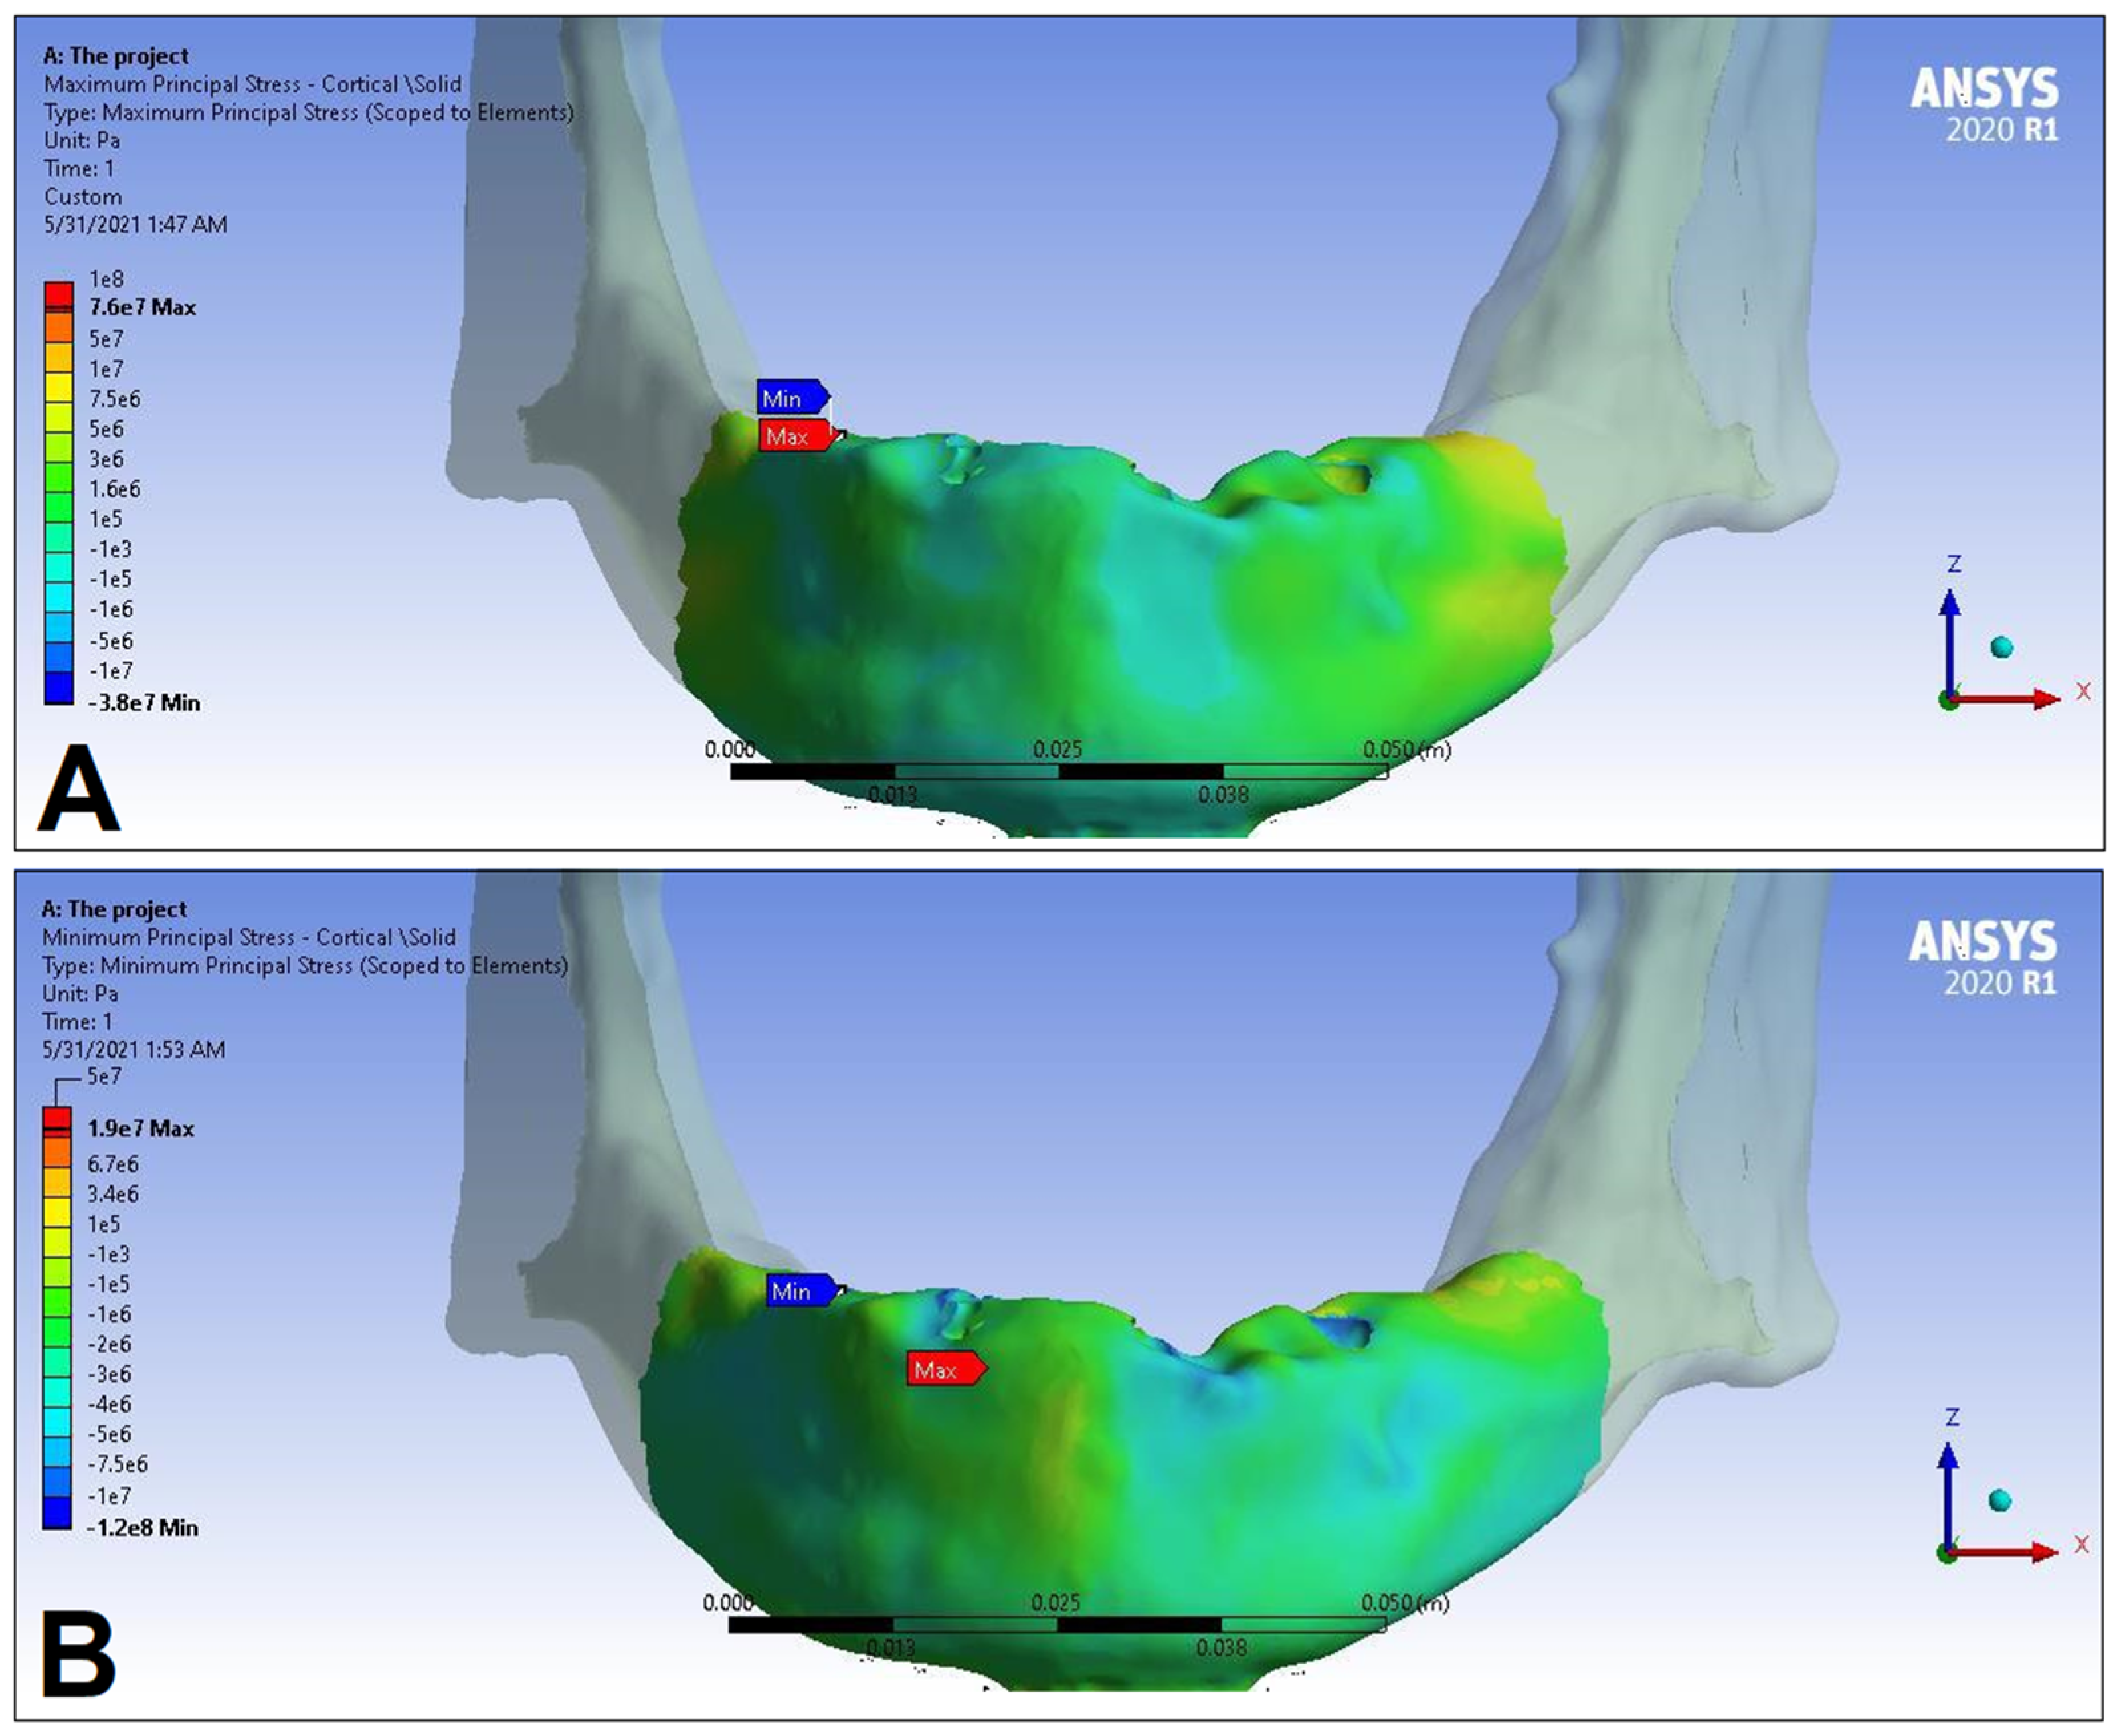

3. Results

| LC1 | LC2 | LC3 | LC4 | ||||||

|---|---|---|---|---|---|---|---|---|---|

| S1 | S2 | S1 | S2 | S1 | S2 | S1 | S2 | ||

| Cortical bone | Pmax [MPa] | 76.39 | 88.51 | 89.57 | 102.98 | 85.63 | 95.48 | 81.02 | 93.15 |

| Pmin [MPa] | −115.30 | −222.76 | −136.4 | −265.35 | −172.30 | −252.61 | −125.20 | −235.32 | |

| Trabecular bone | Pmax [MPa] | 2.49 | 2.24 | 3.03 | 2.62 | 2.95 | 2.52 | 2.92 | 2.59 |

| Pmin [MPa] | −2.81 | −2.89 | −3.34 | −3.38 | −3.25 | −3.25 | −3.49 | −3.52 | |

| Peqv [MPa] | 166.40 | 244.92 | 166.36 | 279.69 | 164.36 | 265.58 | 142.27 | 260.77 | |